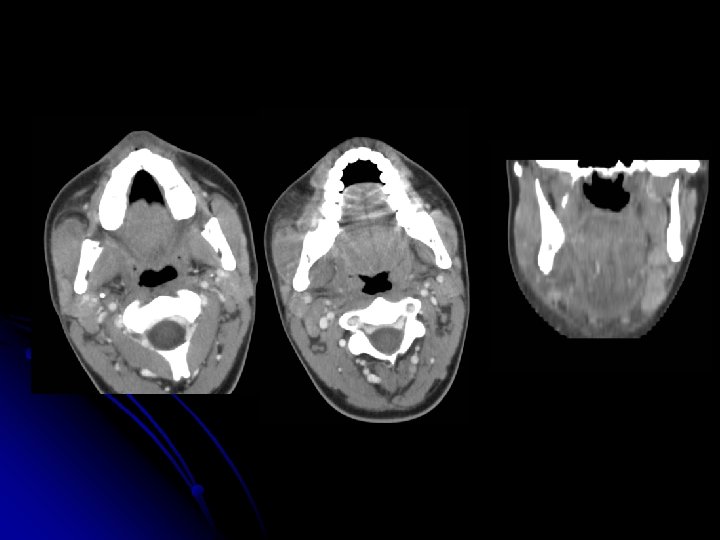

Extensa colección líquida en el espacio masticador derecho con mínima extensión al espacio parafaríngeo, que afecta a la musculatura del masetero, pterigoideos interno y externo con trabeculación de la grasa en vecindad.

Engrosamiento de los músculos masetero y temporal izquierdos por acusados cambios flemonosos. Celulitis grasa adyacente. Colección líquida en fosa infratemporal , en porción medial al masetero izquierdo.

TC hallazgos l l l Cavidad abscesificada Infección cutánea Afectación subcutánea Afectación muscular; miositis ( aumento de tamaño de músculos contiguos) Realce de planos aponeuróticos. La presencia de estas manifestaciones cutáneas y subcutáneas sin colección definida de baja densidad nos hará pensar en celulitis.

Abscesos l l l l CT Zona aislada o multilocular de baja densidad +/- acumulaciones gaseosas realce periférico MR: HIPOINTENSO EN T 1. HIPERINTENSO EN T 2 realce del borde tras la administración de contraste